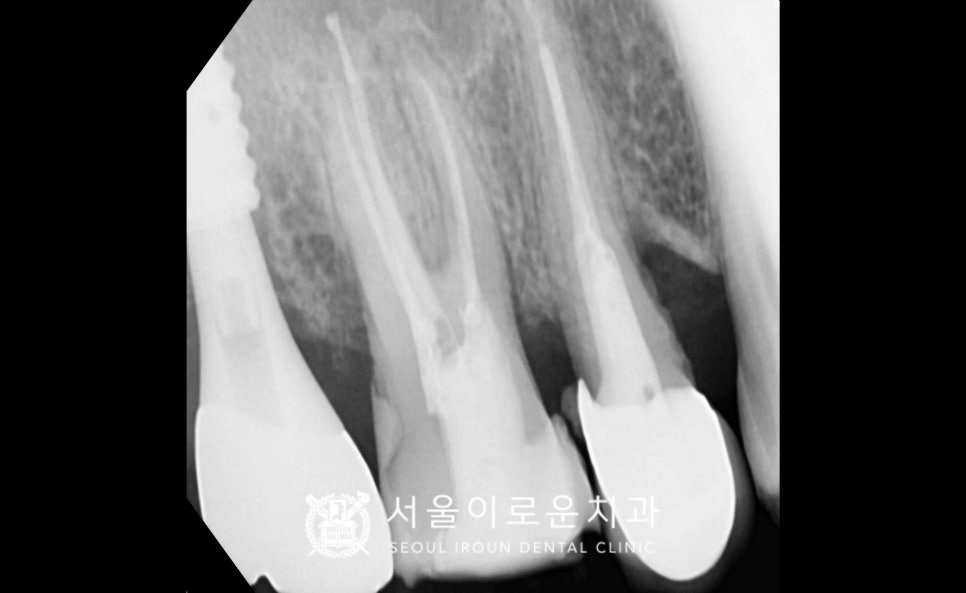

그리고 위턱 첫 번째 큰 어금니(#16)는

충치를 제거한 뒤 확인해 보았더니

치아에 금이 관찰되어

처음 계획했던 인레이 진행이

어려울 것으로 판단되었는데요.

신경치료 + 크라운 수복으로

계획을 변경하였고,

뿌리 끝까지 깔끔하게

신경치료를 마무리한 뒤

크라운 수복까지 성공적으로 도와드렸답니다.